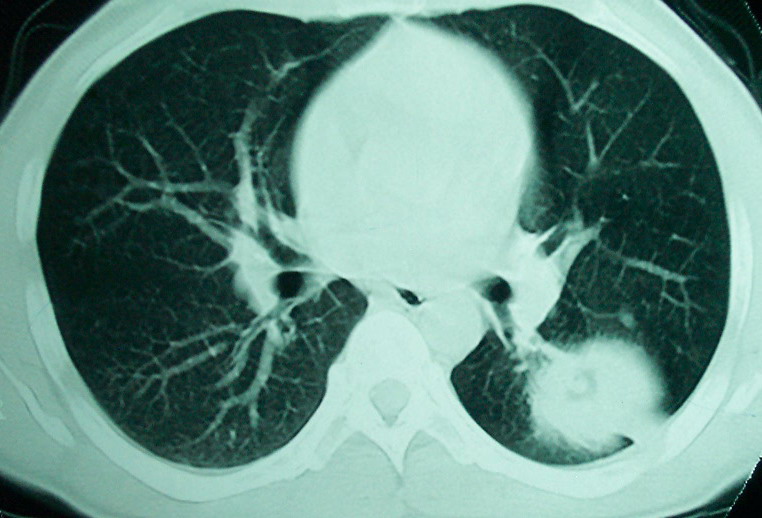

m      37y      发热   咳脓痰月余      ct肺脓肿但住院抗炎治疗后双肺内结节不知该如何解释

治疗后见左肺下野病灶较前缩小但双肺内结节影似无变化请较各位老师该如何下结论    治疗前wbc14.5 治疗后wbc 11.0

1、左下肺鳞癌伴两肺及纵隔淋巴结转移;

2、两上肺支扩伴慢性炎症。

左下肺病灶除了明显的厚壁空洞 气液平外,明显见壁结节,另两肺多发小结节,综合考虑:左下肺周围性肺癌伴肺内转移.

如果你仔细的同层面对比,你会发现所有的病灶均有比较明显的吸收、缩小。病变的形态,特别是脓肿的形态、壁的厚薄、内壁均有很大的变化,均在往好的方面发展。与临床症状、血像均符合,治疗效果比较显著,就是肺脓肿并双肺的化脓性炎症灶。